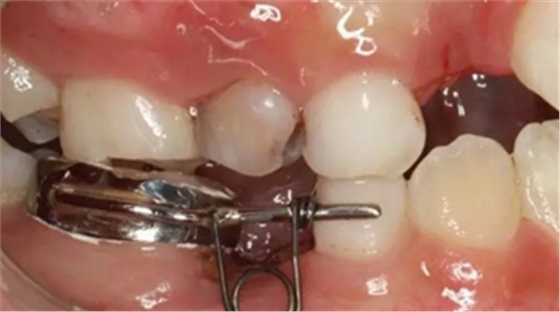

42、牙面拋光,試合制作好的間隙恢復(fù)器,將曲簧水平部分形成與牙面弧形一致,羧酸鋅水門汀粘結(jié)固定

43、粘結(jié)后的頰面觀